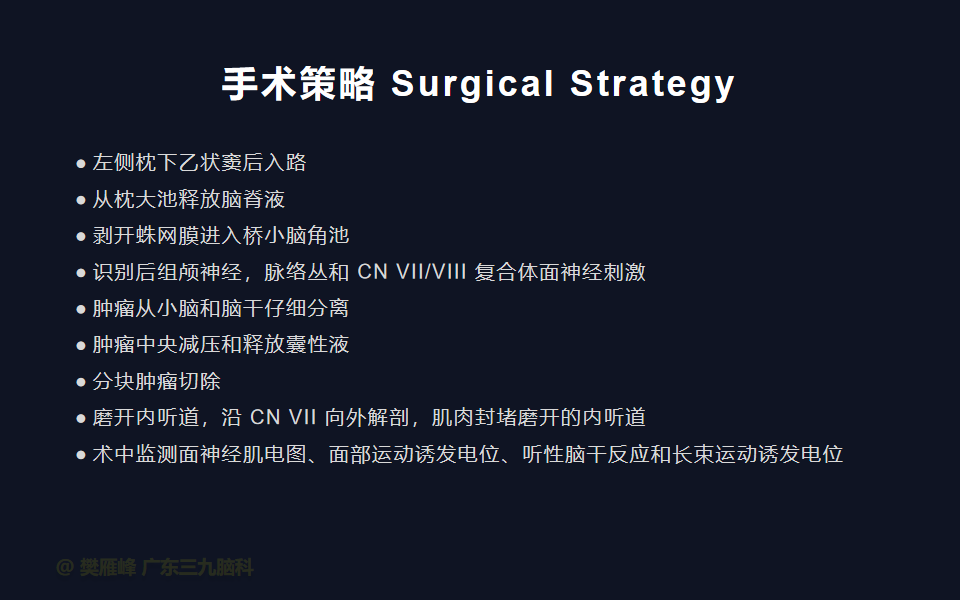

对于直径 > 2.5 cm 的大肿瘤、脑干功能障碍、明显的占位效应、颅内压升高、症状迅速恶化以及任何肿瘤大小的年轻患者(< 50岁) ,不建议进行放射外科手术。这些病变通常需要手术切除。乙状窦后入路被认为是安全和方便,可暴漏全小脑桥角和脑干,降低死亡率和发病率,提高功能性面神经和听力保存率,术前神经症状恢复,并发症发生率低。

在这个二维手术视频中,展示了一种经枕下乙状窦后入路束膜下分离保留面神经的方法。患者是一名51岁的男性,有1年右耳听力下降伴耳鸣、无步态不平衡病史,术前有右侧轻度面瘫,神经影像学显示右侧桥小脑角区约30×30×29mm的囊实性占位,增强后实性部分及囊壁可见明显强化。他接受了经乙状窦后入路保留面神经的方法,术中肿瘤全切除,面神经被肿瘤挤压成薄膜状覆盖于三叉神经表面。术后面瘫加重,听力未能保留,神经影像学显示肿瘤全部切除。我们展示了安全的颅神经保护和肿瘤切除的细微差别和技术要点,以及手术技术。